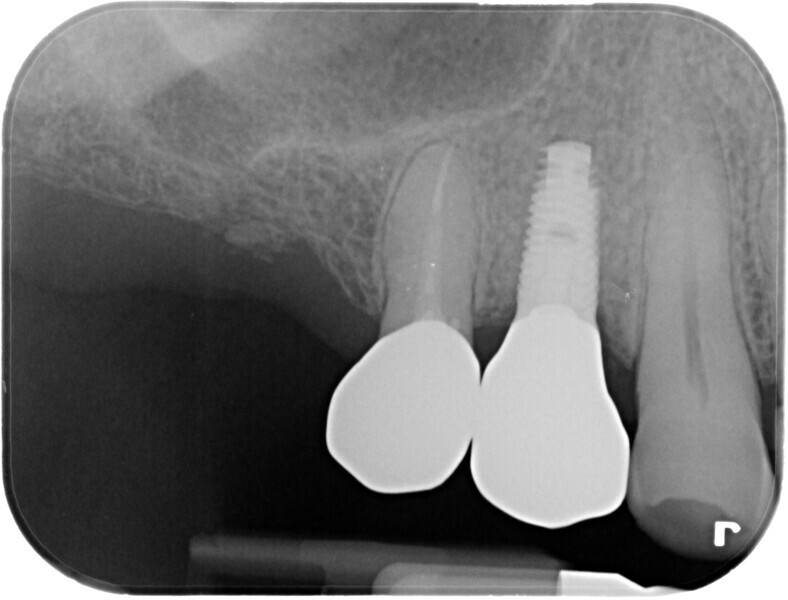

A waiting period of four months allowed adequate osseointegration of the implant (Fig. 20). The endodontic treatment of tooth #15 had been completed in the meantime, and the tooth had been prepared for a complete zirconia crown. Removal of the implant provisional restoration revealed a natural soft-tissue profile and an improved soft-tissue contour without the need for additional soft- or hard-tissue augmentation (Fig. 21).

Secondary impression was taken digitally with an intra-oral scanner and the relevant scan body. Definitive restorations were designed on exocad and milled in-house on CRAFT 5X (DOF) out of EVEREST Multilayer AT zirconia (Shade A3; UNC International). A deliberately lighter shade was chosen by the patient, as he intended to have the appearance of his other maxillary teeth improved. The implant crown was torqued in to 35 N cm, and the crown was cemented to tooth #15 using G-CEM ONE cement (GC Dental; Figs. 22–24).

Fig. 24: Final periapical radiograph, showing the good fit and no excess cement.